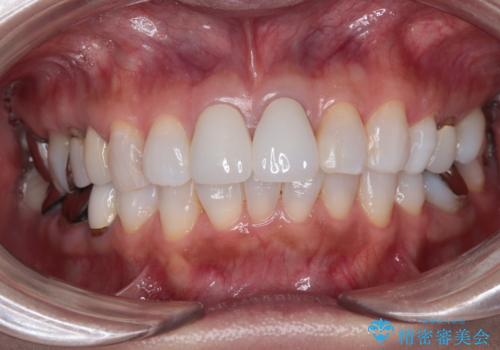

元々の歯の色が非常に白く、セラミッククラウンの色調を合わせるのに苦労しましたが、最終的に大変満足いただけるクラウンを装着することができました。